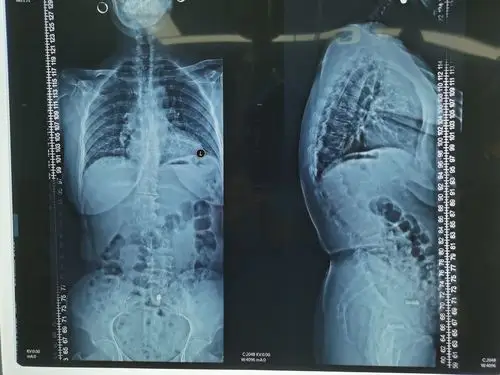

胸腰段后凸cobb角42度,侧凸约20度.